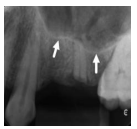

Sobre o uso da Radiologia/Imagiologia Comparativa para a Identificação de Restos Humanos, marque a alternativa correta.